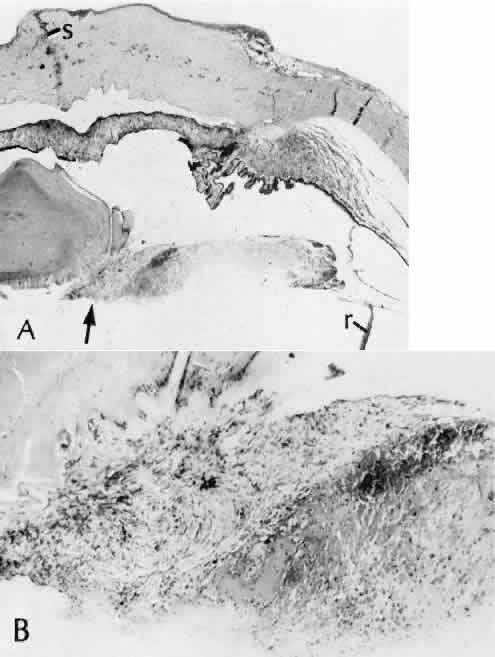

study of the evolution of retinal lesions in the rhesus monkey. American Journal of Ophthalmology 75(4):610–626, 1973. 44. Tso MO, Wallow IH, Elgin S: Experimental photocoagulation of the human retina. Archives of Ophthalmology 95(6):1035–1040, 1977. 45. Wallow IH, Tso MO, Elgin S: Experimental photocoagulation of the human retina. II. Electron microscopic

study. Archives of Ophthalmology 95(6):1041–1050, 1977. 46. Yoon YH, Marmor MF: Rapid enhancement of retinal adhesion by laser photocoagulation. Ophthalmology 95(10):1385–1388, 1988. 47. Miller B, et al: Effect of the vitreous on retinal wound-healing. Graefes Archive for Clinical & Experimental Ophthalmology 224(6):576–579, 1986. 48. Yamana T et al: The process of closure of experimental retinal holes in rabbit eyes. Gaefes Archive for Clinical & Experimental Ophthalmology 238(1):81–87, 2000. 49. Ozaki S et al: Influence of the sensory retina on healing of the rabbit retinal pigment

epithelium. Current Eye Research 16(4):349–358, 1997. 50. Perry DD, Reddick RL, Risco JM: Choroidal microvascular repair after argon laser photocoagulation. Ultrastructural

observations. Investigative Ophthalmology & Visual Science 25(9):1019–1026, 1984. 51. Perry DD, Risco JM: Choroidal microvascular repair after argon laser photocoagulation. American Journal of Ophthalmology 93(6):787–793, 1982. 52. Hayashi A et al: Surgically induced degeneration and regeneration of the choriocapillaris

in rabbit. Graefes Archive for Clinical & Experimental Ophthalmology 237(8):668–677, 1999. 53. Pollack A, Korte GE: Restoration of the outer blood-retinal barrier after krypton laser photocoagulation. Ophthalmic Research 25(4):201–209, 1993. 54. Miller H et al: Pathogenesis of laser-induced choroidal subretinal neovascularization. Investigative Ophthalmology & Visual Science 31(5):899–908, 1990. 55. Jacobs B, Gaynes B, Dutsch T: Refractive astigmatism after oblique clear corneal phacoemulsification